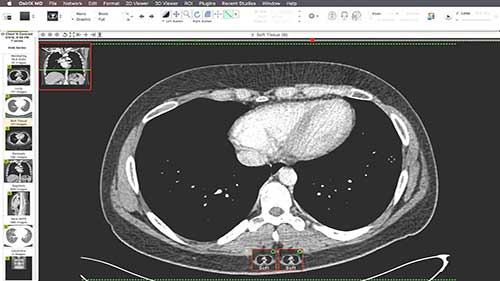

CT造影扫描

CT检查已成为医学影像学非常重要的诊断方法,CT造影的应用范围也非常广泛。在这里,我们将了解在医院进行CT造影扫描的整个流程。